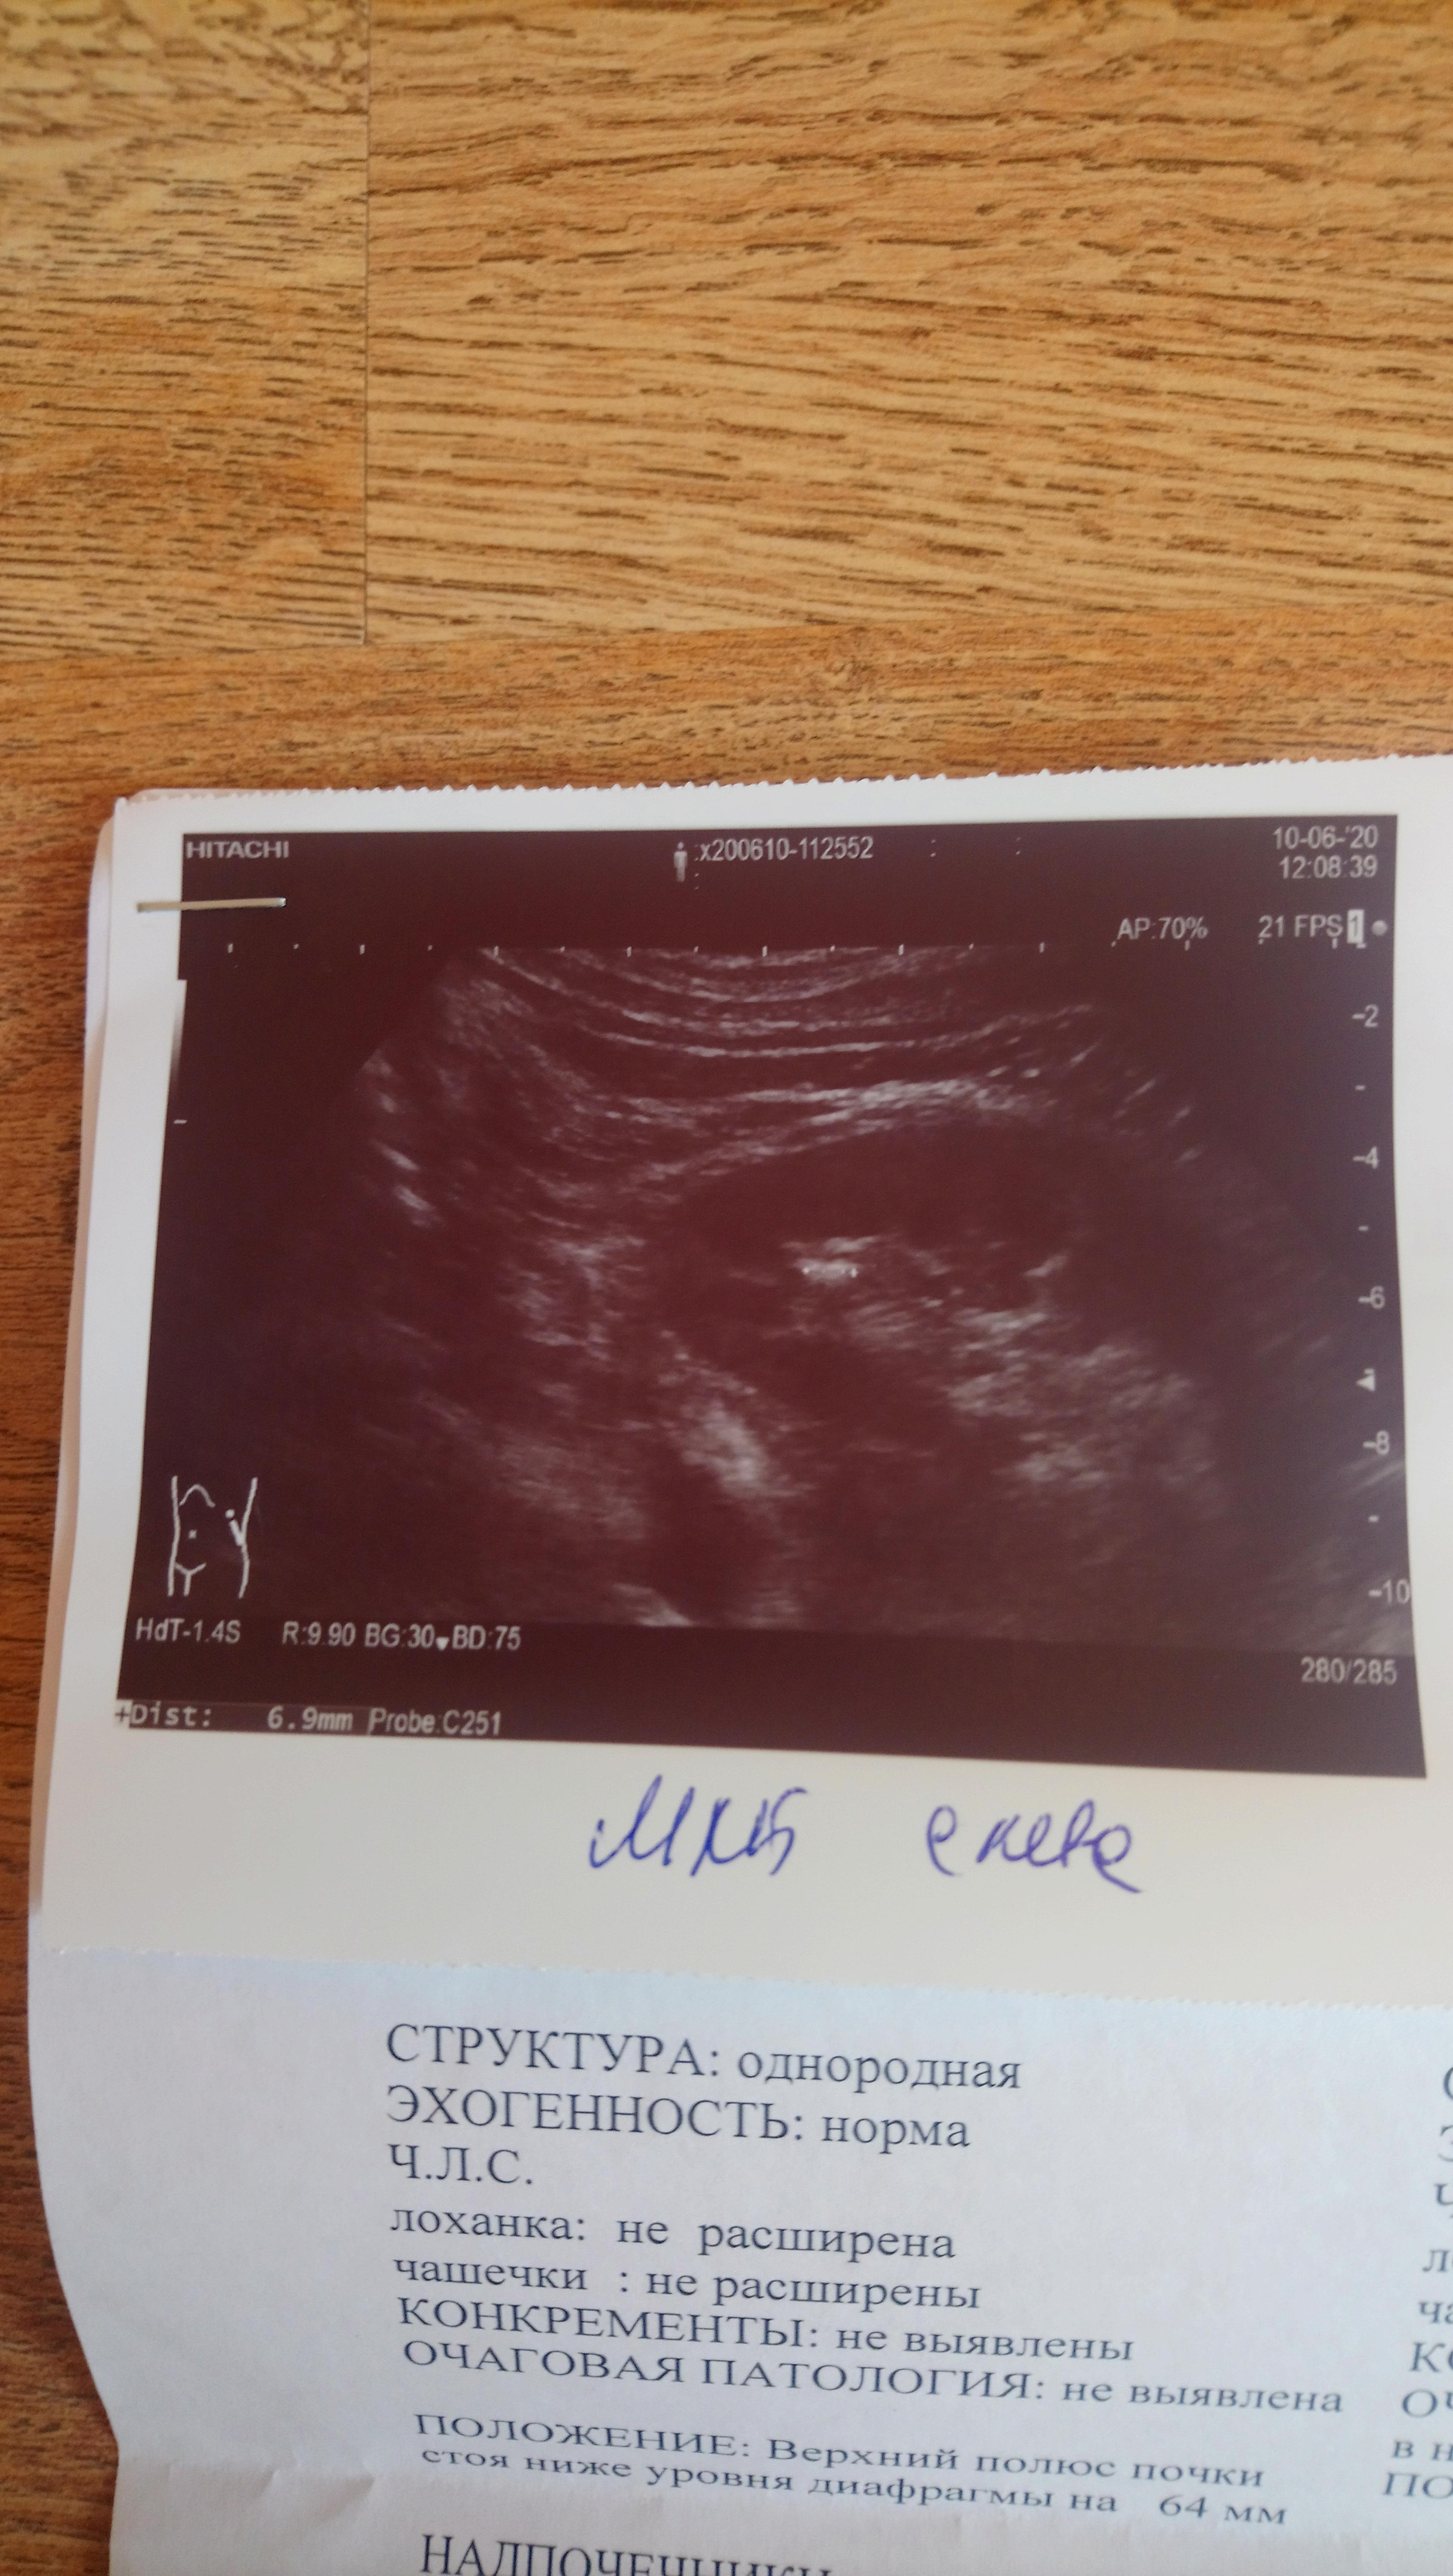

Здравствуйте! Учитывая наличие в моче уратов, можно предпологать , что и конкремент уратный, но необязательно. Целесообразно сделать МСКТ с контрастом - почек и мочеточников ,с 3х мерной реконструкцией. По плотности конкремента можно будет с большей вероятностью предполагать его состав. При конкрементах из солей мочевой кислоты бычно применяют цитратные смеси. При подозрении. по плотности оксалатного характера конкремента, можно рекомендовать комплекс Оксалит. Обсудите эти нюансы с Вашим врачом. Удачи!